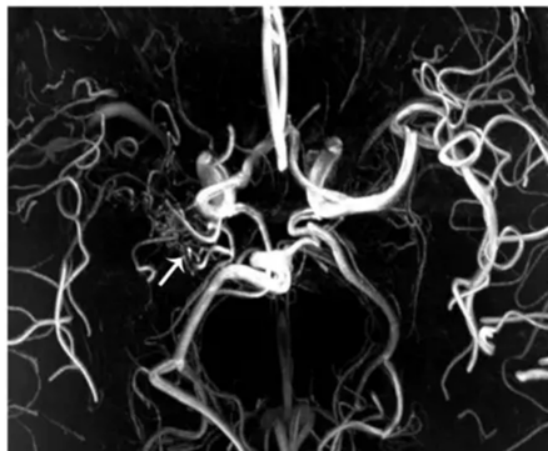

2.磁共振成像(MRI)和磁共振血管成像(MRA):这些无创性检查可以显示脑部血管的狭窄和闭塞情况,以及脑实质的缺血性改变。

MRA